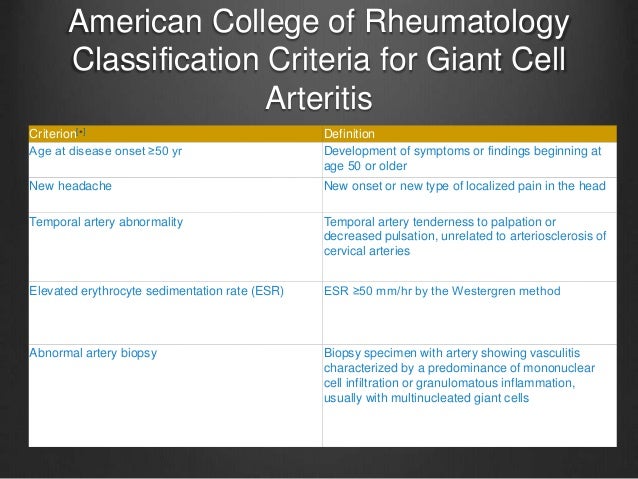

Can GCA cause low red blood cells?

In inflammatory conditions, red blood cells settle more quickly than in non–inflammatory states. In addition, most patients with GCA have a slight–anemia, or low red blood cell count. Other conditions can also cause a high sed rate or anemia, so the final diagnosis depends on a temporal artery biopsy.

Can a temporal artery be removed?

Using a local numbing medication (the same one used by a dentist), the doctor can remove a small part of the temporal artery from under the scalp and look at it under the microscope for evidence of inflammation. A temporal artery biopsy is almost always safe, causes very little pain, and often leaves little or no scar.